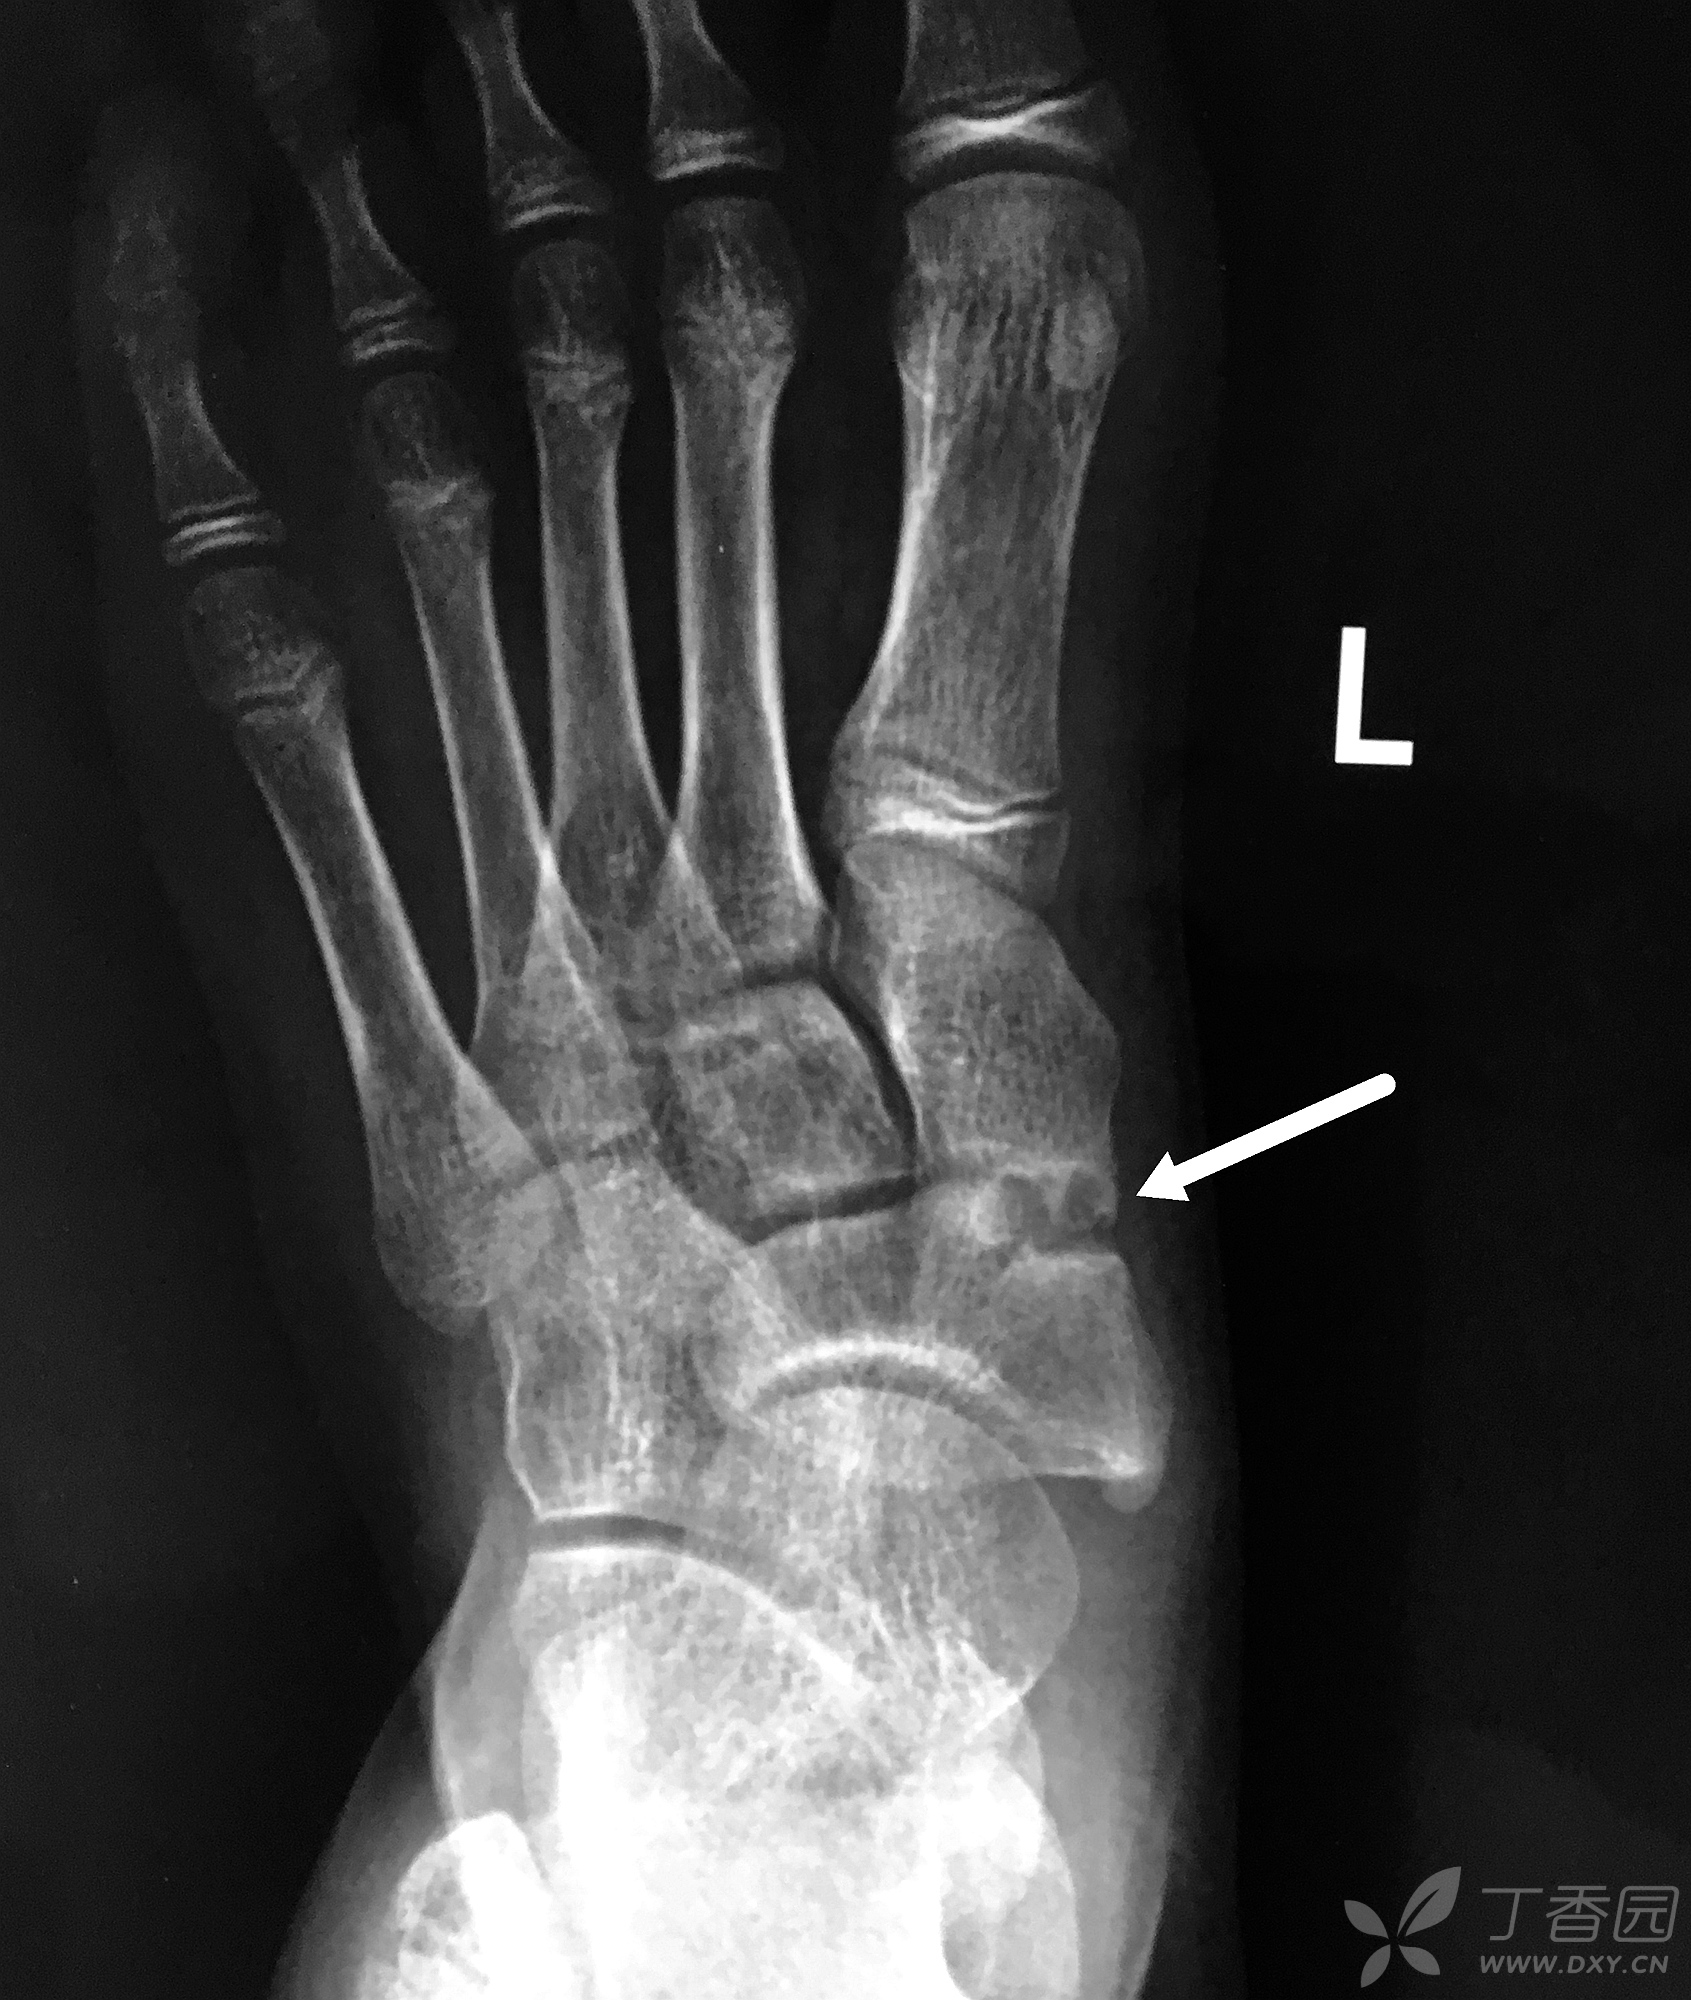

左足舟骨病变,您考虑是啥? [病例帖]

骨科专业讨论版 关节 临床诊断:1,足舟骨骨折(骨骺?陈旧性骨折?